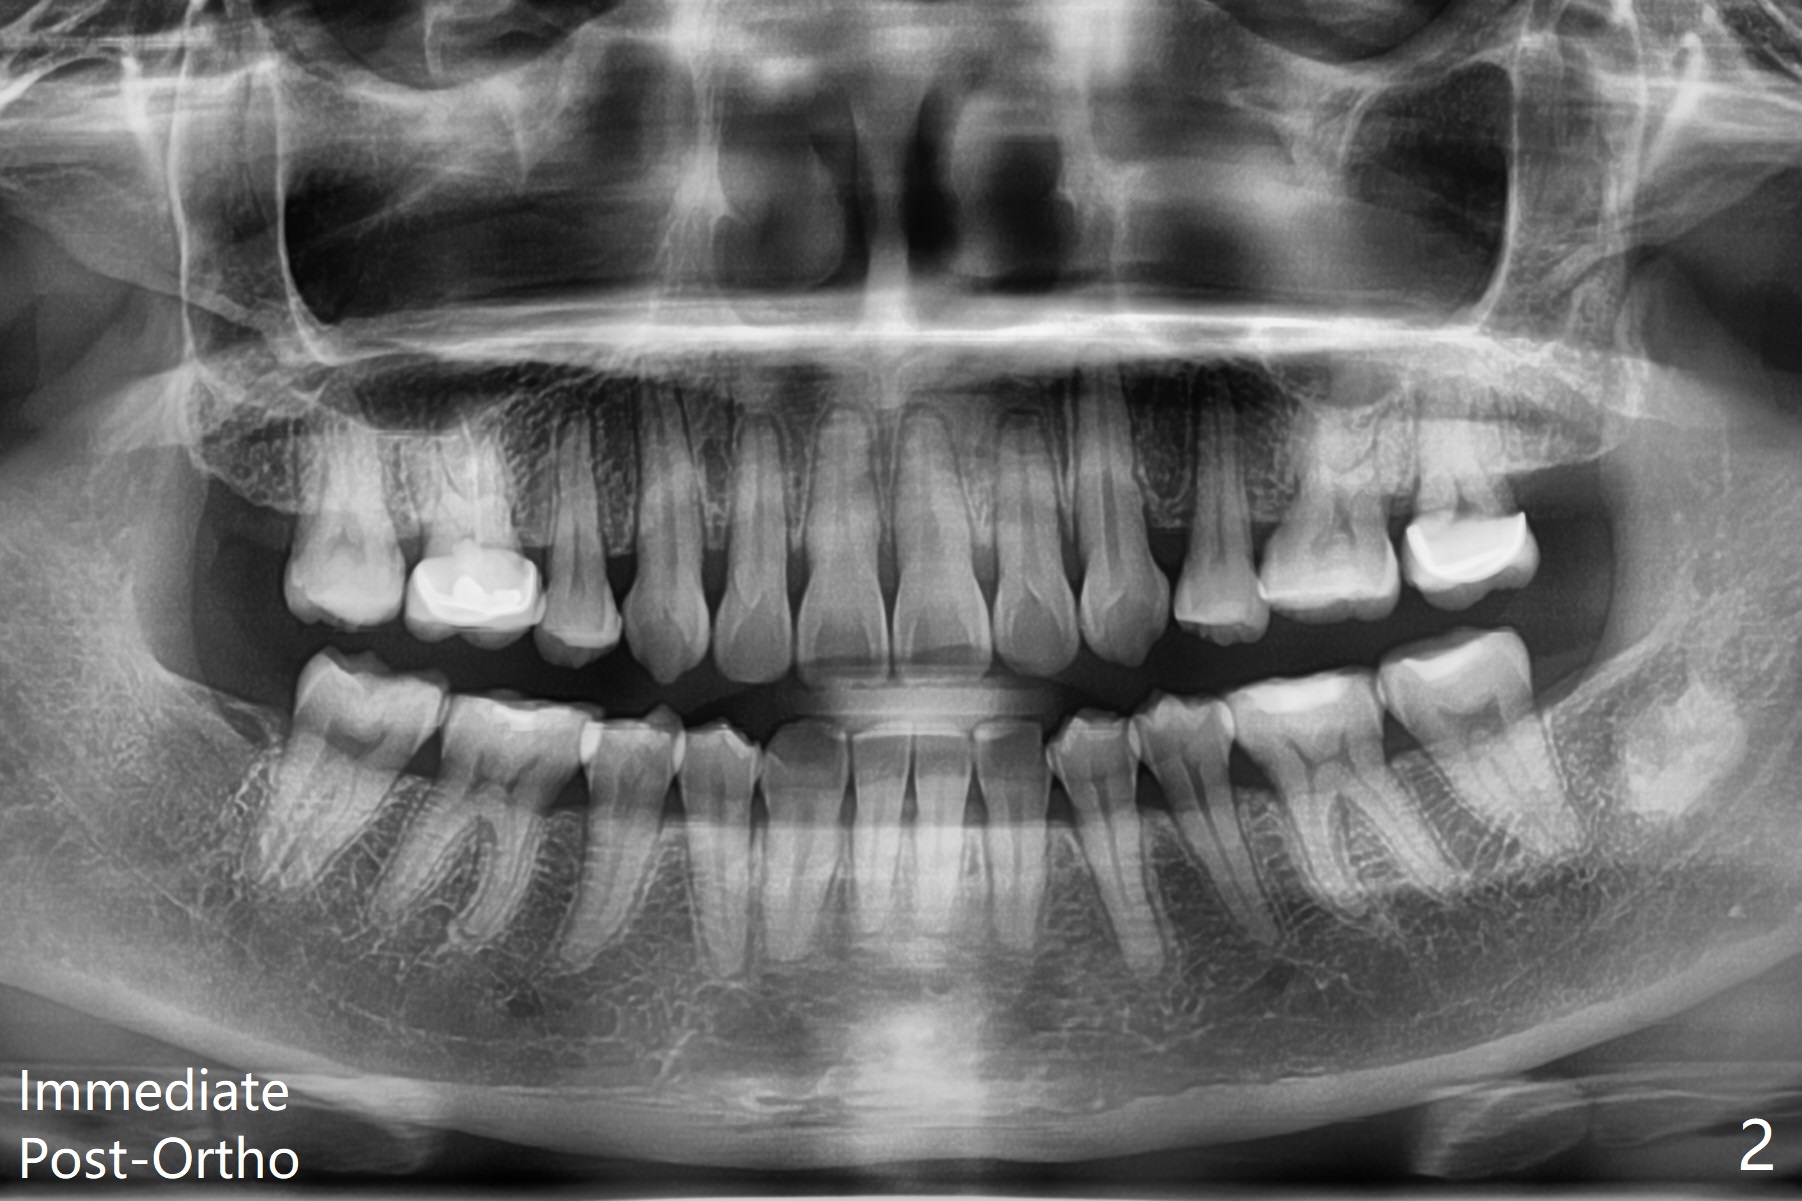

A 41-year-old woman with crowding (Fig.1) undergoes 2.5 year orthodontic treatment with extraction, leading to root resorption of the maxillary anterior teeth (Fig.2-4).